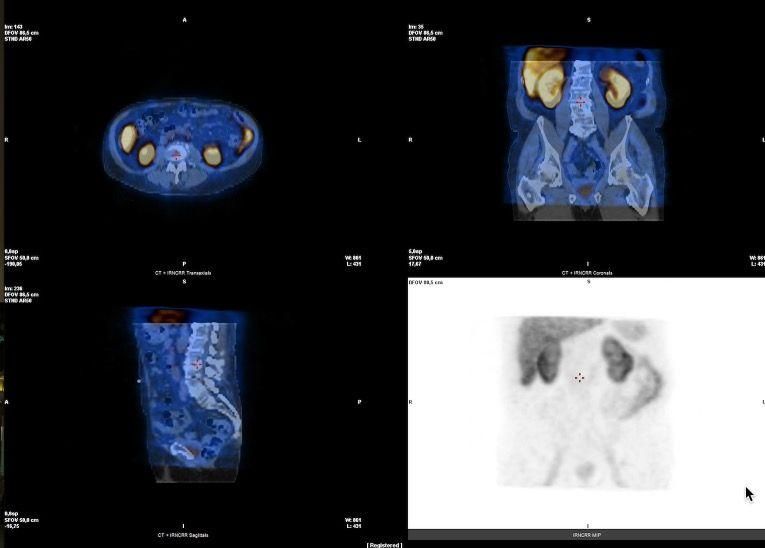

• Prostata PSMA-Rezeptorszintigraphie, bei Patienten mit Rezidiv eines Prostatakarzinoms präoperativ zur Lymphknotenmarkierung bei PSMA-PET-CT positiven Lymphknotenmetastasen